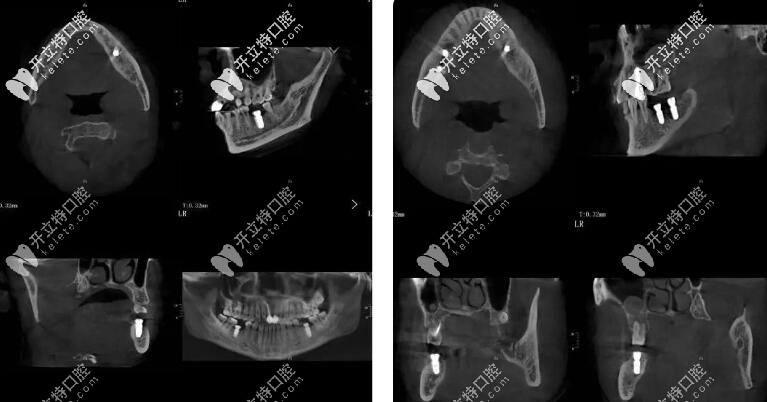

50歲的李先生,長期有不良的口腔習(xí)慣,導(dǎo)致全口牙齒大部分缺失, 現(xiàn)在的情況就是進(jìn)食困難、無法完成咀嚼,再后來顳下頜關(guān)節(jié)紊亂,去了不少醫(yī)院但是解決不了問題。

后來從朋友處打聽到朱院長,朱院長從抬高咬合到頜重建到塊狀骨移植,再從軟組織增量到美學(xué)塑形,解決了李先生的難題。

簡單的來說就是從吃飯咬不動、嚼不碎再到咬合正常,并且恢復(fù)了全口的咀嚼功能。

種植牙手術(shù)